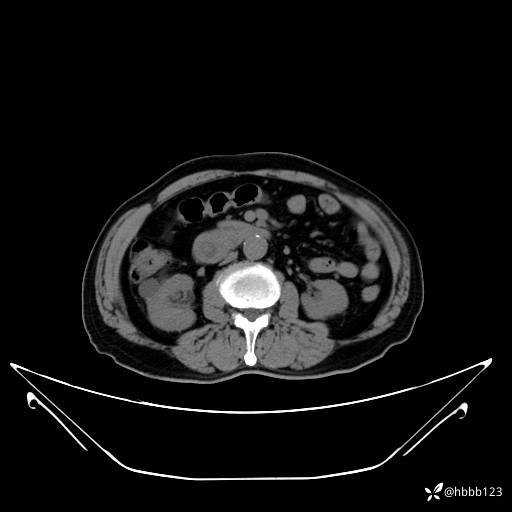

门诊完善上腹部CT平扫+增强扫描:

平扫: